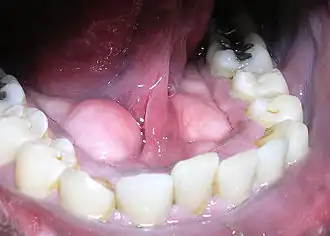

Plaques dentaires d’épaisseur différentiée selon les dents.

La plaque dentaire bactérienne est une substance blanchâtre qui se dépose à la surface de la dent. Elle est essentiellement constituée de protéines salivaires, d'aliments (sucres et acide), de bactéries et des toxines sécrétées par ces dernières[réf. nécessaire].